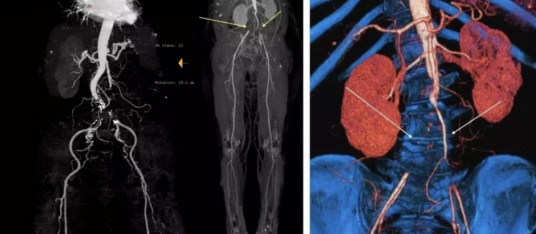

术中因双侧股动脉穿刺均困难,手推造影提示双侧股动脉闭塞。

遂果断另辟蹊径,经肱动脉穿刺成功,行腹主动脉造影证实右侧髂总动脉闭塞,左侧髂总动脉极重度狭窄并串珠样改变,故经股动脉入路此路不通。

头颈部血管造影提示:患者为右侧颈内动脉极重度狭窄合并右侧大脑中动脉闭塞。